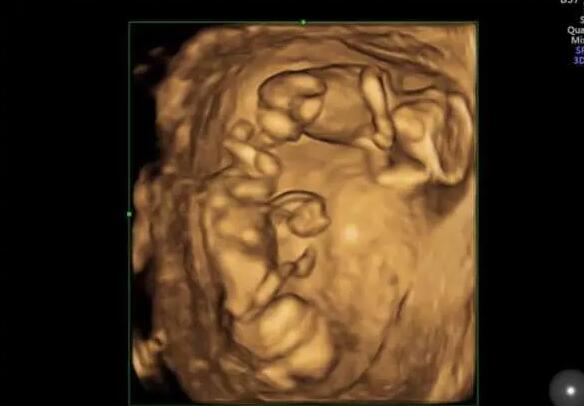

医院简介:目前专业技术人员18人,其中生殖临床医师6人(包括1名男科临床医师),实验室人员5人,护理人员7人。硕士研究生9人。中心由生殖医学临床(包括男科),生殖医学实验室,生殖医学病房三部分组成。生殖医学科是严格按照卫生部[2003]176号文件和省卫生厅的规划要求组建的。成立了院生殖医学伦理委员会,在伦理委员会的监督和指导下开展工作。

试管婴儿的成功率并不取决于卵泡的数量,而是取决于卵泡的质量。因此,卵泡数量少不要太担心,临沂市人民医院做试管婴儿的成功率是相对较高的,临沂市人民医院做试管婴儿的成功率具体如下:

1.临沂市人民医院生殖科每年有近10万名不孕不育症患者接受治疗,完成新鲜、解冻周期超过10000个,总成功率约为53%-55%。在该医院做试管婴儿取卵只有两个卵子,如果两个卵泡的质量较好,即使只有两个卵泡,成功率也相对较高,可以达到50%左右;

2.但是如果卵泡质量不好,成功率会稍微低一些,可能只有30%-40%;

以上就是“2022临沂市人民医院试管婴儿成功率一览,取卵只有2个能成功吗?”的全部内容了,事实上,做试管婴儿并不是卵泡越多越好,即使卵泡的数量再多,质量不好,也是徒劳的。